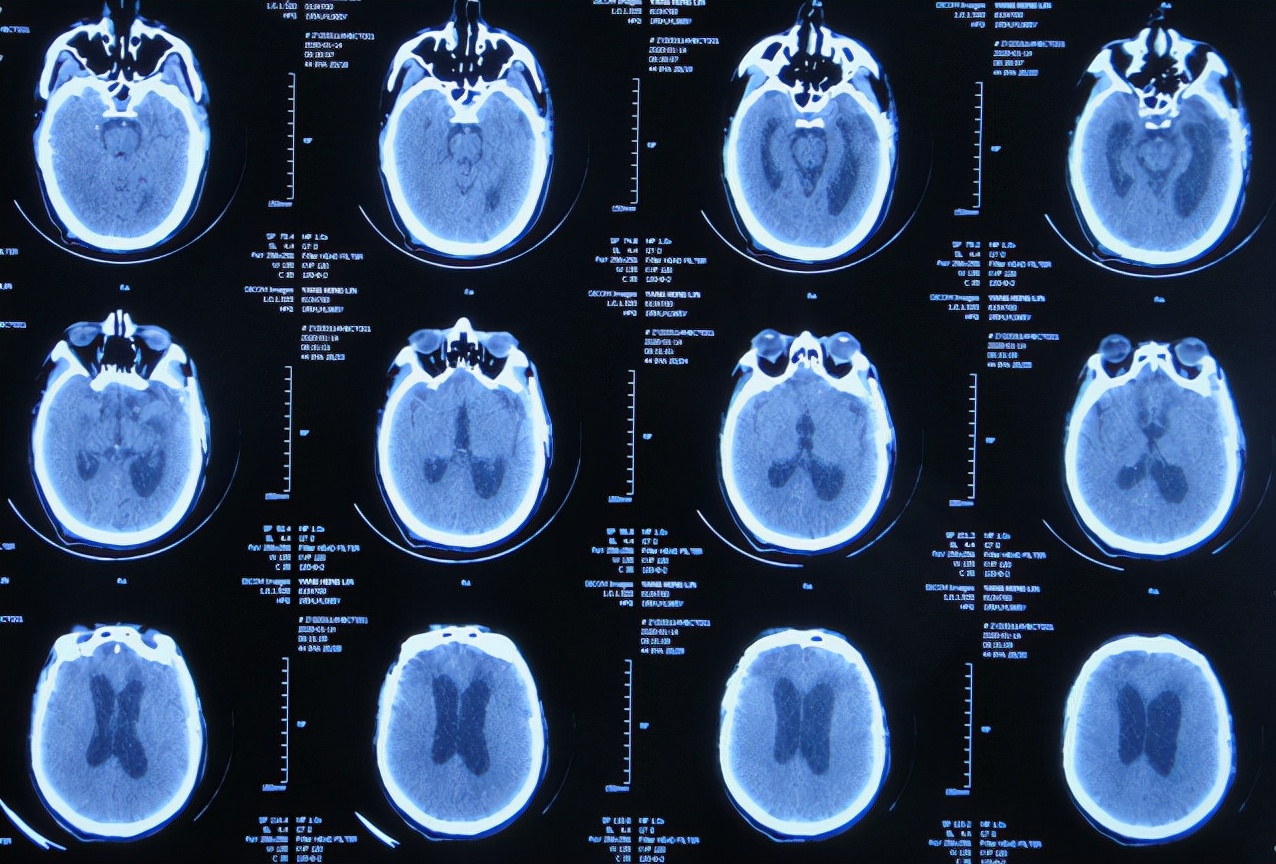

2019年10月20日患者骑电动车在马路上行驶时被大货车撞倒,当时意识清楚,只感到有些头晕,未在意就自行回家,但回家后约3-4小时出现头晕加重,并伴有恶心呕吐的症状,家人急送到当地的河北省邯郸市某医院,查头颅CT示脑出血( 图-1 );既往病史2015年曾因头部外伤致硬膜下血肿,进行了钻孔引流术。

图-1: 2019年10月20日头颅CT

急诊进行了开颅去骨瓣血肿清除术,术后次日查头颅CT示去骨瓣术后( 图-2 )。

图-2: 2019年10月21日头颅CT

开颅术后第2天即2019年10月22日,仍昏迷,查头颅CT示积血未见减少( 图-3 ),给予腰椎穿刺术。

图-3: 2019年10月22日头颅CT

开颅术后第4天即2019年10月24日,查头颅CT示积血仍未明显减少( 图-4 )。

图-4: 2019年10月24日头颅CT